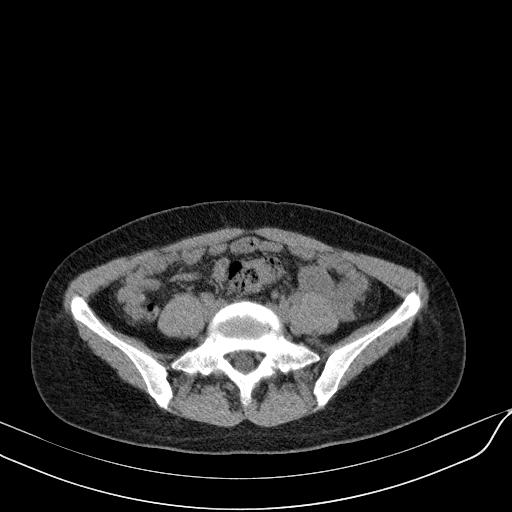

标题: CT23965:无外伤史,下腹痛 [打印本页]

标题: CT23965:无外伤史,下腹痛

无外伤史,下腹部疼痛!---------正常

肠道未准备,继续往下扫,乙状结肠占位不排除。建议钡灌或结肠镜检查。

乙状结肠占位不排除

未见明显异常改变,做个气钡双重造影除外一下结肠病变,无外伤史为啥不常规喝泛影葡胺水对比剂再扫ct呢?

回肠间质瘤?

肠道肿瘤,建议行钡剂灌肠检查。